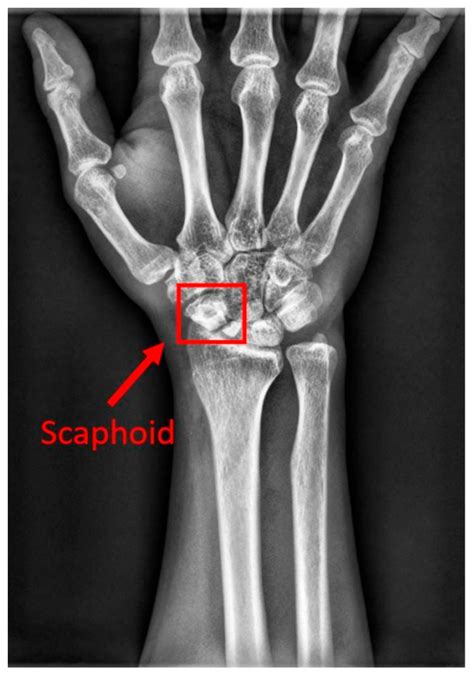

• Imaging Studies: X-rays, CT scans, or MRIs to visualize the abdominal area and identify any underlying issues.